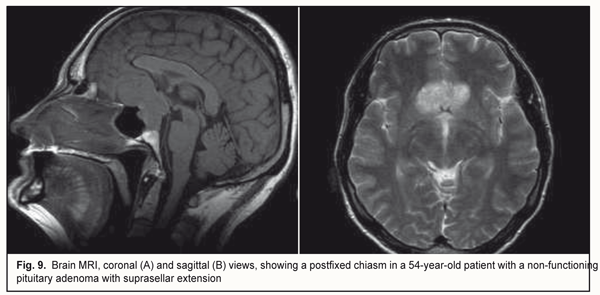

Of the 50 patients with reduced visual acuity and/or or visual field impairment, the hiasm was prefixed in 8 (16%) patients, specifically, in 4 patients with a bitemporal paracentral scotoma, 2 patients with homonymous hemianopia, and 2 patients with a markedly asymmetric visual field (Fig. 8). In addition, the hiasm was postfixed in 3 (6%) patients with a bitemporal constriction of the visual fields (Fig. 9).